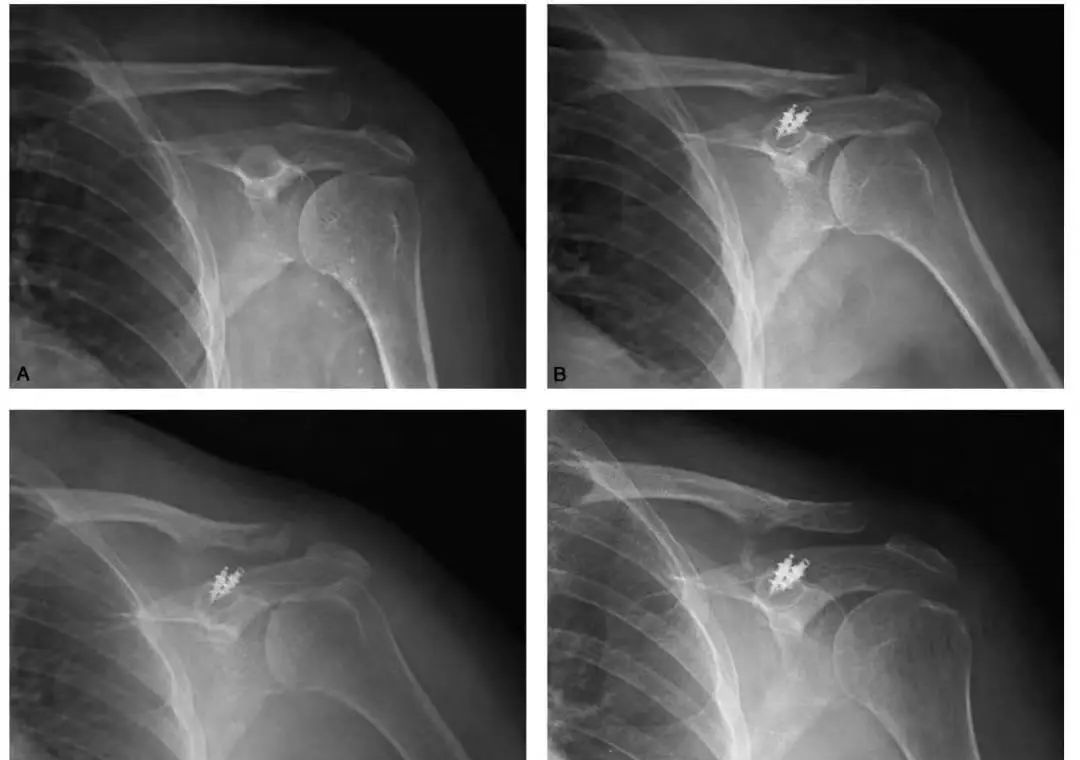

1.锁骨中段骨折

非手术治疗:目前比较一致的观点认为,80%——90%的锁骨中1/3骨折可采取非手术的方法进行治疗,因此非手术治疗锁骨中段骨折一直占据着主导地位。非手术治疗包括多种方法,如对患肢简单悬吊的颈腕吊带、吊带辅以绷带、Sayre绷带、Velpeau绷带等。

锁骨板有哪些【每周科普】锁骨骨折分中段、外段、内段,治疗方式也有差异_https://www.jmylbn.com_新闻资讯_第11张

手术治疗:主要手术方式有髓内固定接骨板系统两种。

手术治疗的绝对适应证包括:开放骨折、合并血管损伤、进行性神经受损的表现、漂浮肩、移位的病理骨折以及原始骨折短缩>2cm。相对适应证包括:合并有多发伤、皮肤受损潜行剥脱、双侧锁骨骨折、无法忍受长时间制动、对外形美观有较高要求以及存在帕金森症、癫痫、颅脑损伤等神经精神情况。

锁骨板有哪些【每周科普】锁骨骨折分中段、外段、内段,治疗方式也有差异_https://www.jmylbn.com_新闻资讯_第12张

锁骨中段骨折的接骨板内固定手术